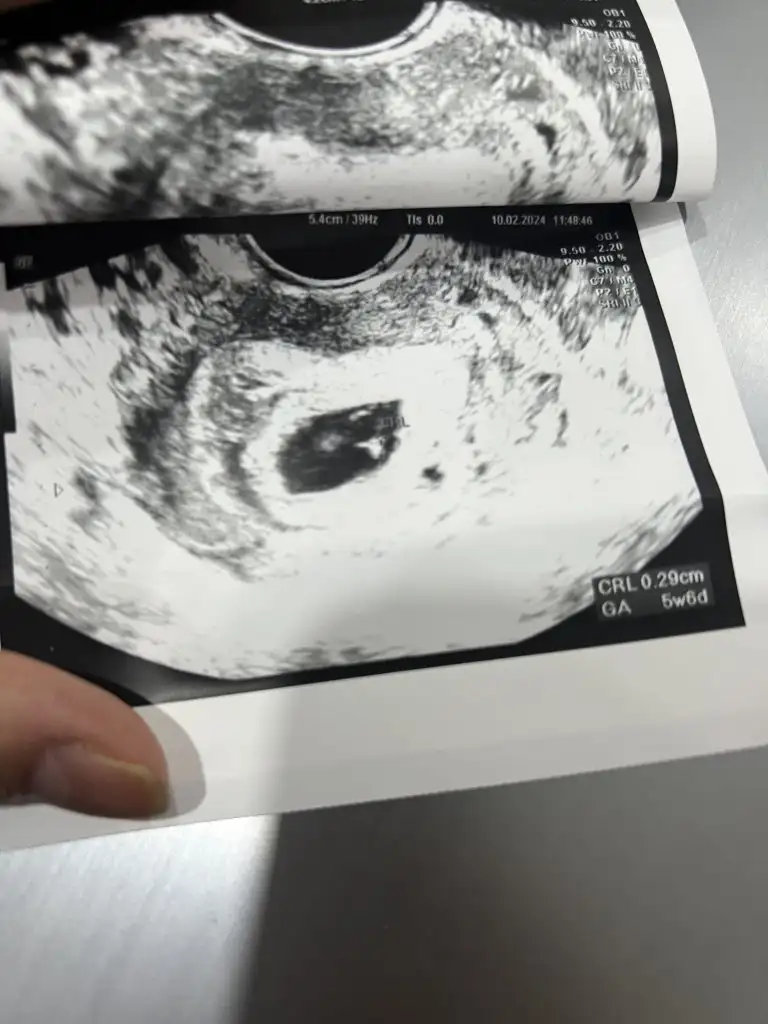

6haftalık vajinal ultrason

Cinsiyet tahmini

Selam bana da tahminde bulunabilir misiniz?